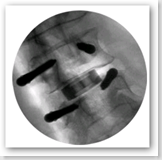

A new medical grade silicon nitride for orthopedic surgeries..the article states they are ghost-like under X-ray imaging...BD

The Valeo VBR spinal implant is intended for vertebral body replacement to aid in surgical correction and stabilization of the thoracolumbar spine. The Valeo VBR incorporates Amedica's novel silicon nitride ceramic, which provides new functionalities compared to competing devices currently on the market. The implant is designed to restore the biomechanical integrity of the anterior, middle and posterior spine, even in the absence of fusion, for a prolonged period of time.